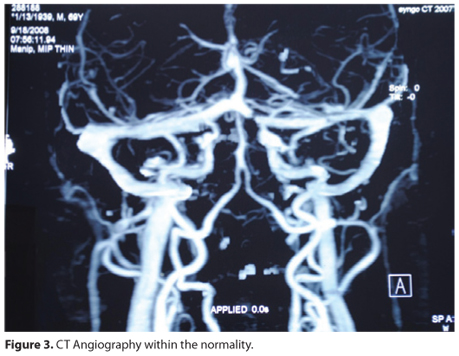

A male patient, aged 69 years old, was admitted to the ophthalmology service with chronic hyperemia of the left eye, which was unresponsive to medical treatment, without other ocular symptoms (Figure 1). He had normal cranial tomography. In his first assessment in 2008, the patient presented with 20/20 visual acuity bilaterally and with normal fundoscopy, without dilation or increased tortuosity of the retinal vessels, as demonstrated by retinography (Figure 2). The intraocular pressure measurement was 14 mmHg in the right eye and 25 mmHg in the left eye, which had dilated episcleral vessels. Biomicroscopy of the left eye showed increased tortuosity and venous engorgement of the conjunctiva and episclera. The patient was treated with antiglaucoma eye drops, which reduced the intraocular pressure to 20 mmHg. The episcleral vessel dilation persisted, and CT angiography, obtained to investigate the possibility of arteriovenous fistula, was negative (Figure 3).